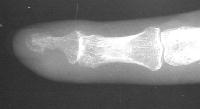

Clinical Example: Breast cancer metastatic to fingertip

Breast cancer is known to metastasize widely. This patient with poorly differentiated breast cancer developed a fingertip mass. Biopsy confirmed metastasis, but she declined further surgery.

Telangiectatic skin vessels and regional hyperemia consistent with active tumor angiogenesis.